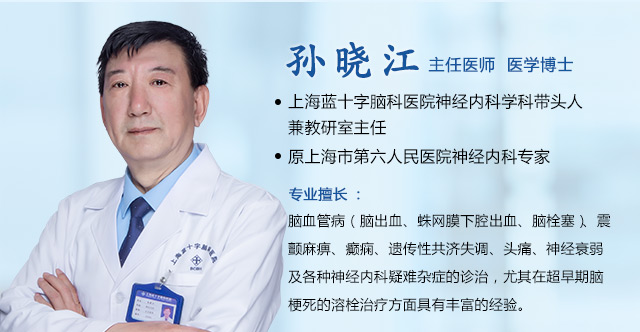

上海蓝十字脑科医院【同济大学附属脑科医院(筹)】脑血管病二科4B病区主任潘登博士指出:后循环梗死的症状往往不典型,易与其他疾病混淆,可能表现为:头晕或眩晕、视物重影、呕吐、行走不稳、言语含糊、口周或面部麻木、肢体麻木等。

“头晕”加“口唇麻木”,竟是脑干梗死

在众多因头晕就诊的患者中,精准识别出后循环缺血,考验着医生的经验与判断力。不久前,潘登博士接诊了一位六旬的女性患者 。她因“头晕、口唇麻木一天”前来就诊,没有出现肢体无力、言语不清等典型中风表现。凭借丰富的临床经验,潘登博士在详细了解病史后,高度怀疑是后循环梗死,立即为她安排了头颅磁共振检查。

磁共振弥散加权成像(DWI)结果显示:脑干区域可见明确的斑片状高信号影,对应的ADC图呈低信号——这是新发脑干梗死的影像证据。脑动脉成像同时提示血管轻度硬化,右侧椎动脉V4段纤细。基于对后循环缺血的深刻认识和对影像细节的敏锐把握,潘登博士结合影像与临床症状,迅速明确了诊断,为患者争取了宝贵的治疗时间。

“这位患者症状看似轻微,但DWI影像显示脑干已发生急性缺血损伤。脑干结构精细、功能关键,即使小范围梗死也可能带来严重后果,或是更重症风险的前兆。”潘登博士说。